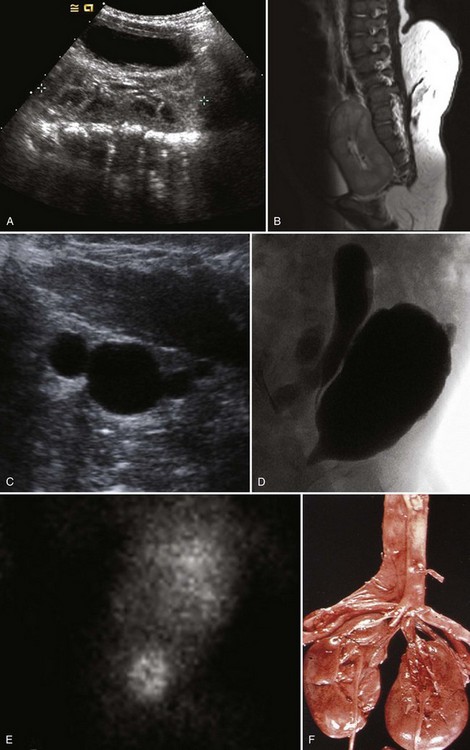

Figure 117–10 One-day-old boy with a right retrovesical pelvic kidney demonstrated on (A) transverse ultrasonogram of right pelvis. B, Sagittal MRI. Vertebral abnormalities and a portion of a lipomyelomeningocele are also observed. C, Longitudinal ultrasonogram of left multicystic dysplastic pelvic kidney. D, Voiding cystourethrogram shows reflux into dilated, tortuous right megaureter. E, Flow study of dimercaptosuccinic acid shows early activity only in the region of the right pelvic kidney and no uptake on the left. F, Postmortem specimen from a different case showing bilateral pelvic ectopia, anterior orientation of renal pelves, and anomalous blood supply from the aortic bifurcation.

(C, Courtesy of Dr. Sara Milla; F, from Weiss MA, Mills SE. Atlas of genitourinary tract disorders. Philadelphia: JB Lippincott; 1988.)